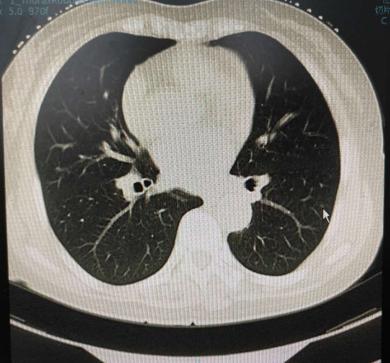

问症状,患者仅有微咳嗽,胸闷,舌质淡,苔薄白,脉弦细。考虑为寒痰凝结,温化寒痰治疗一个月后查ct,影像及报告见下图: